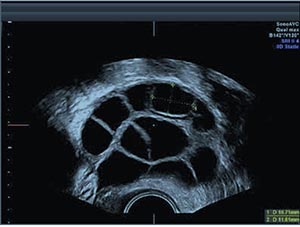

3- متابعة نمو البويضات:

يجب متابعة إستجابة المبيضين للحقن المنشطة للتبويض بإستخدام جهاز الموجات فوق الصوتية (السونار) من خلال المهبل، والهدف من هذه المتابعة الأتي:-- متابعة نمو الحويصلات التي تنمو داخلها البويضات حتى تصل إلى الحجم المناسب .

- تجنب حدوث التنشيط الزائد للمبيض.

- تحديد توقيت سحب البويضات.